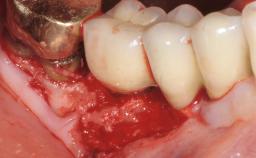

Late Presentation of Peri-Implant Mucositis Requiring Soft-Tissue Augmentation and Esthetic Crown Lengthening at Implant Site 11